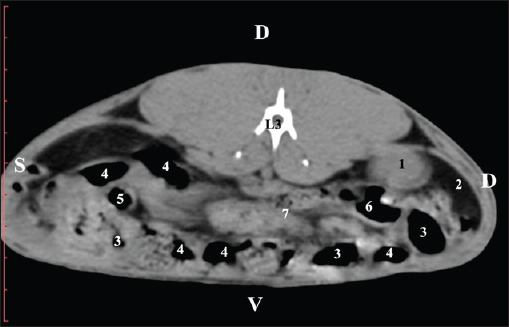

Fig. 7. Pre-contrast computed tomography (CT) anatomical scan of the regio-abdominis media at the caudal L3 edge level. (1) Ren dexter; (2) adipose collection; (3) cecum; (4) colon ascendens; (5) colon transversum; (6) colon descendens; (7) mesenterium. The transverse pre-contrast examination of the regio abdominis media at the L3 level (through the cranial part of the vertebra) revealed the left kidney’s extremitas cranialis as an oval soft tissue with normoattenuated soft tissue characteristics. Ventrally, the kidney was adjacent to the duodenal pars ascendens, ileum, colon ascendens, and colon descendens. Hypoattenuated abdominal adipose collections were observed around it (Figs. 8 and 9).

Fig. 8. Pre-contrast computed tomography (CT) anatomical scan of the regio-abdominis media at the cranial L3 edge level. (1) Ren sinister; (2) adipose collections; (3) cecum; (4) colon ascendens; (5) jejunum; (6) pars ascendens of the duodenum; (7) colon descendens; (8) colon transversum; (9) colon descendens.